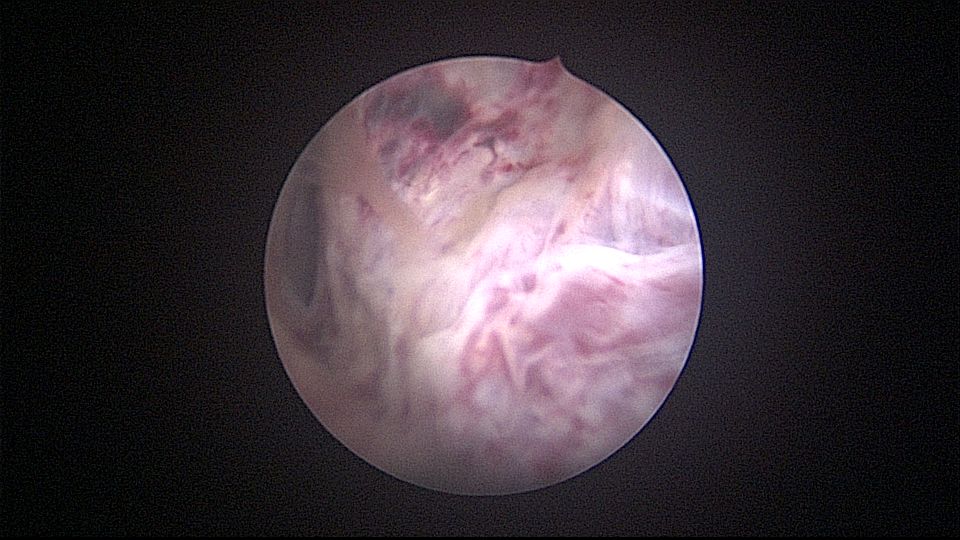

患者32岁,G6P2,顺产2次。2025年3月,停经56天,计划外妊娠,要求终止妊娠并放置节育环,考虑终止妊娠后宫腔大,担心环移位或脱落,要求固定节育环。γ环没有尾丝,用4号丝线连接环及不锈钢挂钩,将挂钩插入宫底肌层固定,异物钳原位固定曼月乐,退出宫腔镜,结束手术。术后患者未回院复查节育环位置。